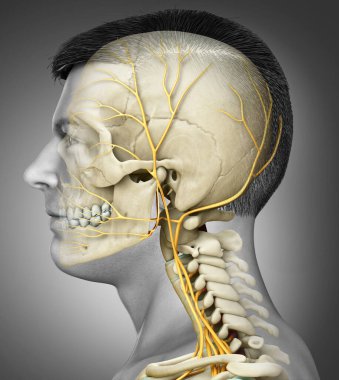

iskelet adam yan görünüm baş ve sinir sistemi

En Çok Aranan Kelimeler

resimlemeİnsanSağlıksağlıklıYaşamkanSağlık hizmetleriTıbbiboğazıçizgi filmsemboldişlerKardiyolojikalpnabızgövdeÇizimbiyolojiBilimbölümgemigerçekçiGöğüsorgBilimselanatomidiyagramPompaGergintedavülarterAtriumApexanatomikSinirlerdolaşımaortkoronerventrikülİnsan Vücududamar sistemiPulmoner fizyolojisiFiziksel bölümdolaşımı kanAnatomi gözlerBenzer İçerikler